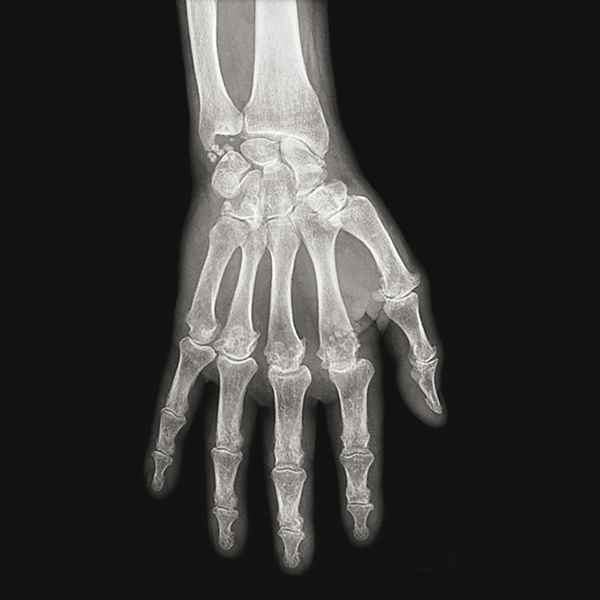

Radiographie de main et de poignet de face. Chondrocalcinose du ligament triangulaire du carpe. Pincement et ostéophytose en hameçon des articulations métacarpo-phalangiennes 2, 3 et 4. Tiré de : Guggenbuhl P, Coiffier G, Albert JD, Chalès G. Dossier. Arthropathies microcristallines. Rev Prat 2015;65(5):665-82.